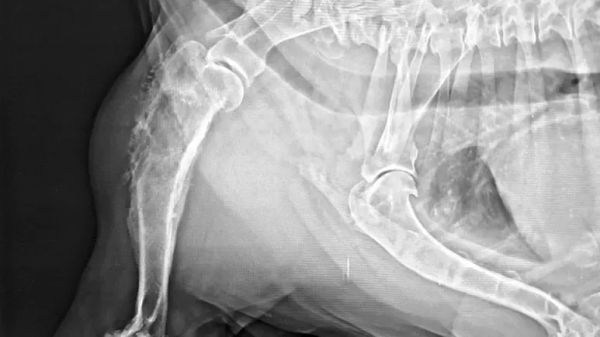

At this time of year, you can't be too careful when you take your pet outside. If this widely spread menace enters your pet's body through their eyes, ears, mouth, nose, skin, feet or genitals, it can quickly become a one-way deadly battle since your pet's body can't degrade or remove them.